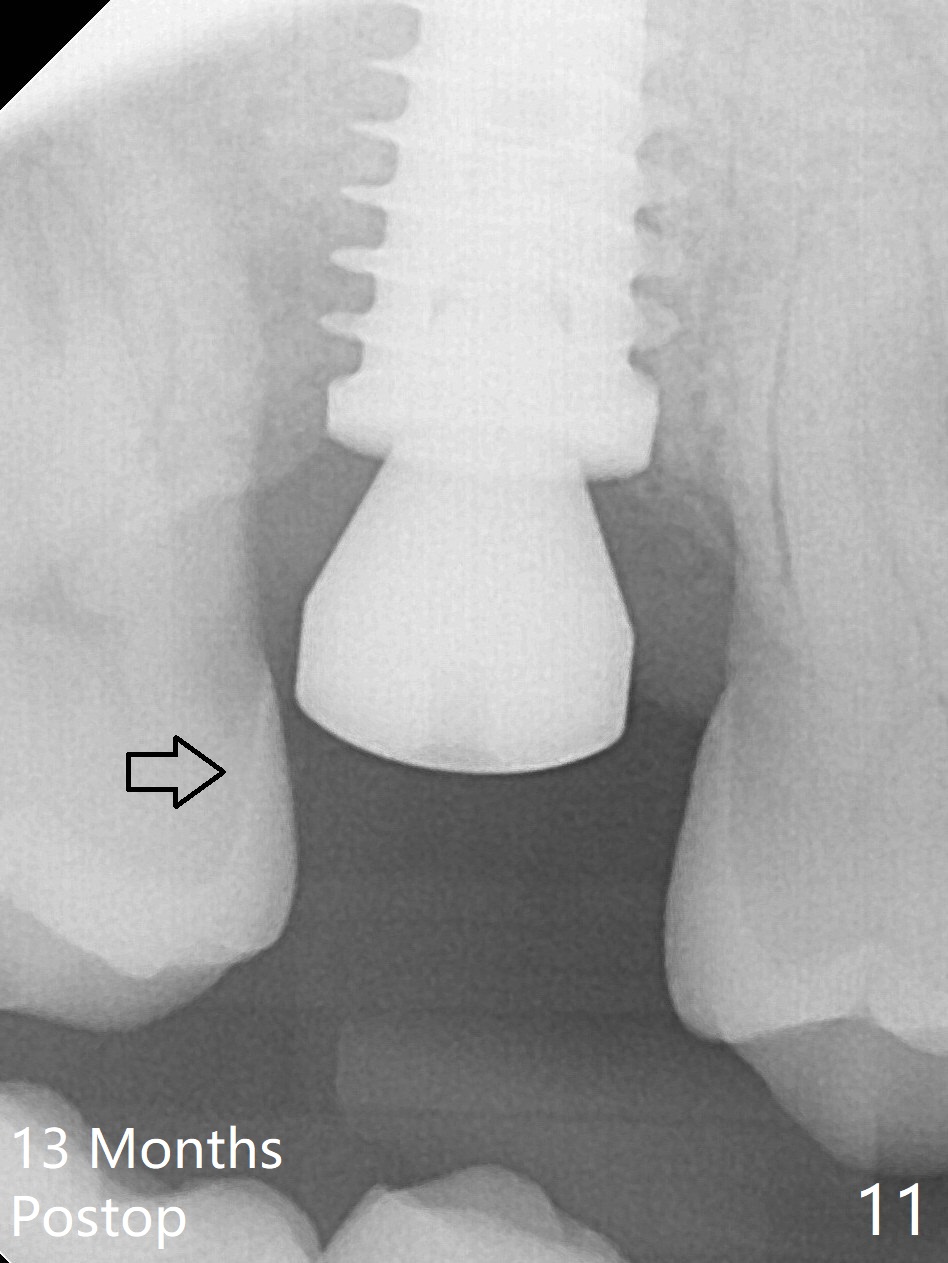

When the 59-year-old man returns for #24 implant placement, the tooth #2 is found to have crack (Fig.1,2 arrowheads), associated with buccal and palatal fistulae (*) and loss of amalgam (Fig.4 *). Abundant granulation tissue is attached to the roots of the affected tooth (Fig.3), indicating severe bone loss. There is a plateau associated with the septum and buccal sockets, which is the site of osteotomy. Magic split and 3 and 3.8 mm Magic Expanders are used to initiate osteotomy. After use of 4.3 mm Magic Drill for about 3 mm, Osteogen plug and allograft are used for sinus lift, followed by insertion of a 4.5x11 mm dummy implant (Fig.5). When a 5.5x9 mm dummy implant is placed with stability, it appears to be seated cervical (Fig.6,7). When a 6x9 mm IBS implant (definitive) is placed with a 6.5x5.5(4) mm abutment, they are seated too deep for provisional (Fig.8). The implant/abutment are removed and replaced by a 6.5x11 mm one in a shallower position; after trimming the same abutment as mentioned above (Fig.9), an immediate provisional is fabricated to keep bone graft in place. Fabrication of Tap with soft tissue markers will reduce the chance of miscalculation and waste of implants. The coronal threads of the implant are covered with bone 6 months postop (Fig.10). One month later when a permanent crown tries in, the implant is found to be loose and tender. A healing abutment is placed. Six months later, the patient returns for crown retry-in. The tooth #1 seems to have shifted mesially (Fig.11 arrow). When the abutment is placed, the implant remains tender and loose. After implant removal with a wrench, there is no granulation tissue or bony defect, including the intact sinus floor (Fig.12 <). Since the tooth #1 has deep periodontal pockets and mobility, the tooth is extracted with abundant granulation tissue. After debridement, Osteogen plug is placed in the socket of #1, while Vanilla graft is placed at the site of #2 (Fig.13 *). Three weeks later, the socket of #2 heals with exposure of Osteogen plug (Fig.14 (B: buccal)).